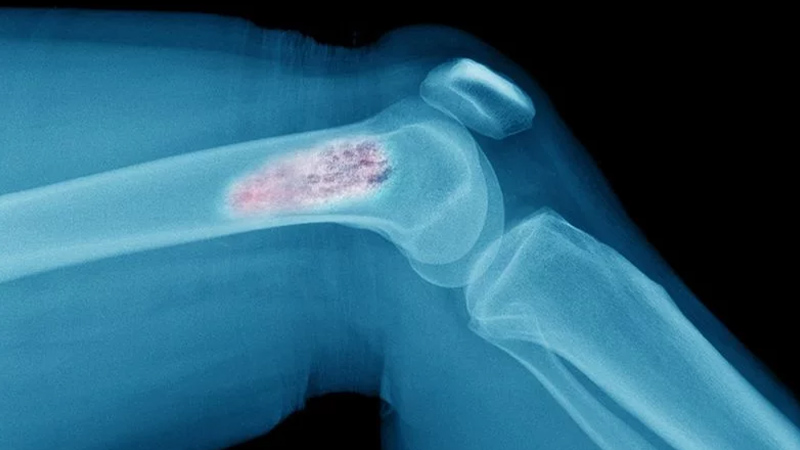

İyi huylu kemik tümörleri genellikle yavaş ilerliyor ve eklem ya da kemikte ağrı, hareket kısıtlılığı ve aksama gibi şikâyetlerle ortaya çıkabiliyor. Bu tümörlerin bir kısmı düzenli takiple kontrol altında tutulabilirken, kırık riski veya hızlı büyüme potansiyeli olanlar cerrahi müdahaleyle temizlenebiliyor. Kötü huylu kemik kanserlerinde ise şiddetli ve giderek artan kemik ağrısı, tümöre bağlı kırıklar ve şişlik gibi belirtiler öne çıkıyor.

Kemik ve yumuşak doku tümörlerinin teşhisi radyolojik tetkikler (grafi, MR, tomografi, PET-CT) ile konuluyor. Geniş cerrahi operasyonların ardından protez, plak-vida ve çiviler kullanılarak kemik sağlamlaştırılıyor. Osteosarkom ve Ewing sarkom gibi bazı kötü huylu tümörler özellikle çocukluk ve ergenlik döneminde acil tedavi gerektiriyor.